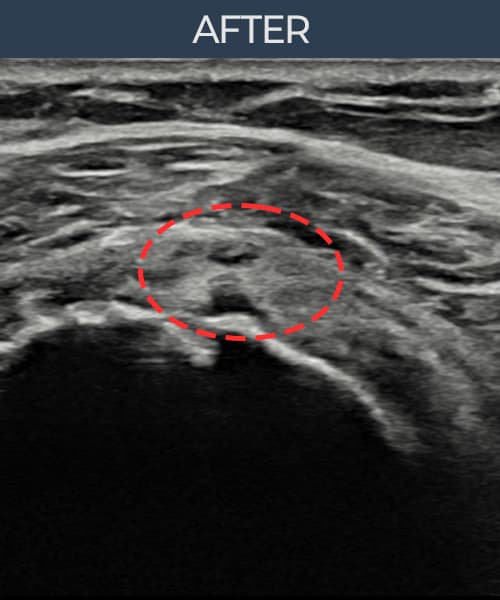

[촬영시기:23.07.18~23.09.14]

[어깨인대 축소봉합술] 좌측 어깨 광범위 파열로 수술을 권유받았으나 비수술 치료를 원해 내원하셨습니다.